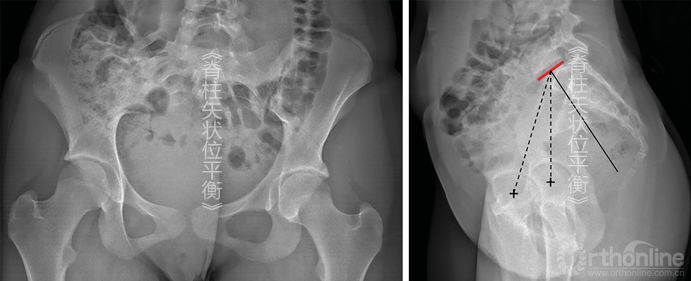

有一些L5/S1关节发育异常,当L5骶化时,L5/S1退变间盘可作为测量PI的参照物;当S1腰化时,S1上终板可作为参照物(图5-4);有时实在无法分辨时,脊柱的大致形态对于选择椎间盘用于测量PI角会有所帮助。无论在何种情况下,如果骶骨上终板无法辨认,则PI角无法测量。

图5-4 腰骶处异常 A.S1和S2椎间盘退变,通过S1上终板辨认PI;B.L5骶化,通过S1上终板测量PI